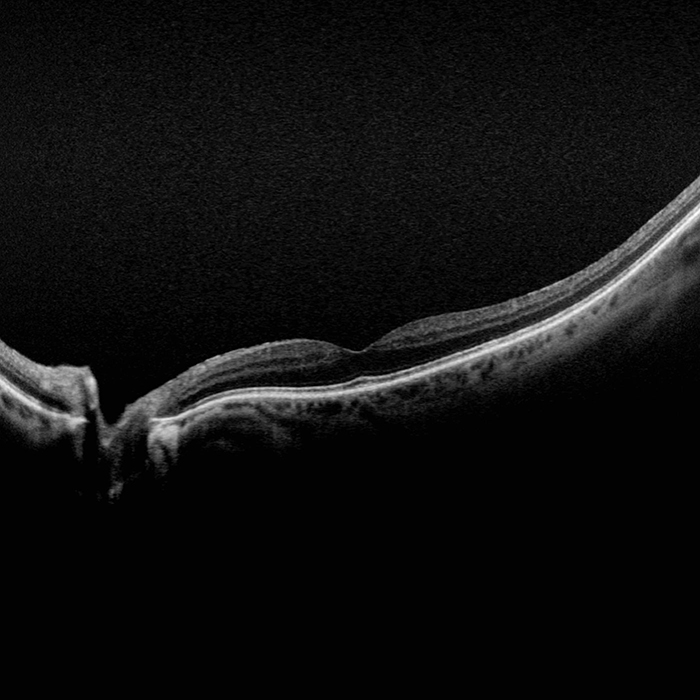

Silverstone RGB redéfinit l’excellence dans l’imagerie rétinienne. Seul équipement capable de produire des images optomap ultra grand champ à 200° en une seule prise, parfaitement intégrées à un OCT swept-source guidé. Pour la première fois, les professionnels de la vue ont accès à neuf modalités d'imagerie performantes dans un seul système, chacune étant conçue pour visualiser les pathologies où qu'elles se trouvent sur la rétine.

Il est démontré que l’optomap améliore la détection, la prise en charge des pathologies ainsi que le flux des patients. Maintenant disponible avec neuf modalités d’imagerie, y compris un OCT Swept-source intégré, Silverstone RGB facilite l'examen de la rétine du vitré jusqu’à l’interface choroïdo-sclérale.

- OCT-SS

- OCT : Balayage linéaire jusqu’à 23 mm et fonction swept-source